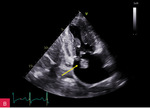

W badaniu echokardiograficznym przezklatkowym (TTE – transthoracic echocardiography) uwidoczniono guzowatą zmianę o wymiarach 37 × 28 × 25 mm u podstawy tylnego płatka zastawki mitralnej i w obrębie ściany dolno-bocznej lewej komory, o nierównej powierzchni od strony komory, nieznacznej ruchomości zgodnej z ruchem serca i niejednorodnej echostrukturze ze zwapnieniami (ryc. 2-5). Powodowała ona niewielkie ograniczenie ruchomości płatków zastawki mitralnej z utrudnieniem napełniania komory i parametrami małej stenozy (ryc. 6). Stwierdzono ponadto małą niedomykalność mitralną (ryc. 6), dużą niedomykalność trójdzielną, znacznie powiększone obydwa przedsionki oraz w niewielkim stopniu prawą komorę w zakresie drogi odpływu, a także niewielki przerost ścian lewej komory. W badaniu nie stwierdzono wyraźnych odcinkowych zaburzeń kurczliwości lewej komory. Globalna funkcja skurczowa lewej i prawej komory była zachowana w dolnych granicach normy: frakcja wyrzutowa lewej komory (LVEF – left ventricular ejection fraction) 50%, skurczowe przemieszczenie płaszczyzny pierścienia trójdzielnego (TAPSE – tricuspid annular plane systolic excursion) 18 mm. Stwierdzono cechy dysfunkcji rozkurczowej lewej komory z cechami wysokiego ciśnienia napełniania. Zarejestrowano również małą ilość płynu w osierdziu (do 6 mm za ścianą boczną lewej komory).